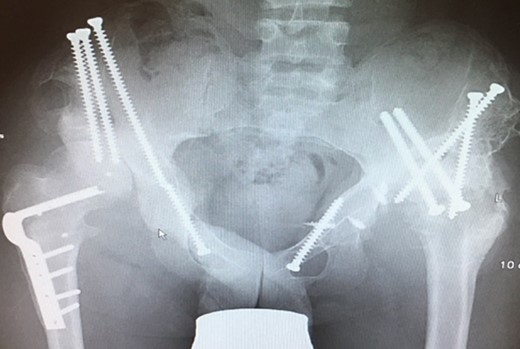

(A + B): (2008) (A) Hip reconstruction with open reduction, Tönnis triple pelvic osteotomy and shortening rotational varus osteotomy of the left femur demonstrating correct deep reposition in ap view. (B) Lauenstein view shows that the acetabular congruency over the femoral head is restored.

Ten years ago, a 12-year-old male presented to our clinic complaining about limping and massive swelling of the left hip. Figure 1 shows the initial X-ray and the 3D reconstruction of the left hip at first presentation when the femoral head, had already destroyed the lateral edge of the acetabulum like a mortar. Severe pain episodes have apparently not been noticed and a former hip dysplasia was not known. A brief clinical history revealed that the patient presented repeated episodes of finger biting and fevers from 2 to 8 years old. The intelligence level of the patient was at an average. The patient was admitted to a paediatric neurologist and a genetic test. A mutation of the NTRK1 gene was found and the diagnosis of CIPA was established. The right hip initially appeared to be normal and the patient was walking, therefore surgical reconstruction for the left hip was proposed due to massive swelling, inability of normal walking and significant limb length discrepancy. A Tönnis/Kalchschmidt triple pelvic osteotomy with open reduction and a shortening varus derotation osteotomy (VDRO) of the femur was performed (Fig. 2A–B). After 3 months the patient was walking again but another 3 months later the hip dislocated again without severe pain. Although the femoral head was already damaged the hip joint was reconstructed again by open reduction, capsular reconstruction with suture anchors and a trevira tube and a movable external fixator was used to temporary stabilize the joint (Fig. 3). The right hip at this time was still intact and was protected with a pneumatic orthotic device. A few months later in 2009, despite all surgeries, the left hip had entirely lost congruency and the right hip developed subluxation despite conservative treatment (Fig. 4). The patient was still walking so the decision to reconstruct the right hip with open reduction, capsular augmentation with a trevira tube, a triple pelvic osteotomy and VDRO was made (Fig. 5). Few months later this reconstruction failed as well and the hip dislocated without severe pain (Fig. 6).